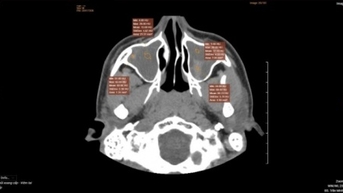

ការរីកចម្រើនគួរឱ្យកត់សម្គាល់មួយទៀតគឺការថតមុនការវះកាត់នៃច្រមុះ និងប្រហោងឆ្អឹង។ វេជ្ជបណ្ឌិត Florian Bast មកពីប្រទេសអាឡឺម៉ង់នឹងបង្ហាញការប្រើប្រាស់បច្ចេកវិទ្យារូបភាពទំនើបដូចជា CT និង MRI ដើម្បីបង្កើនប្រសិទ្ធភាពដំណើរការវិនិច្ឆ័យ បង្កើនភាពត្រឹមត្រូវ និងគាំទ្រវេជ្ជបណ្ឌិតក្នុងការសម្រេចចិត្តព្យាបាលសមស្រប។